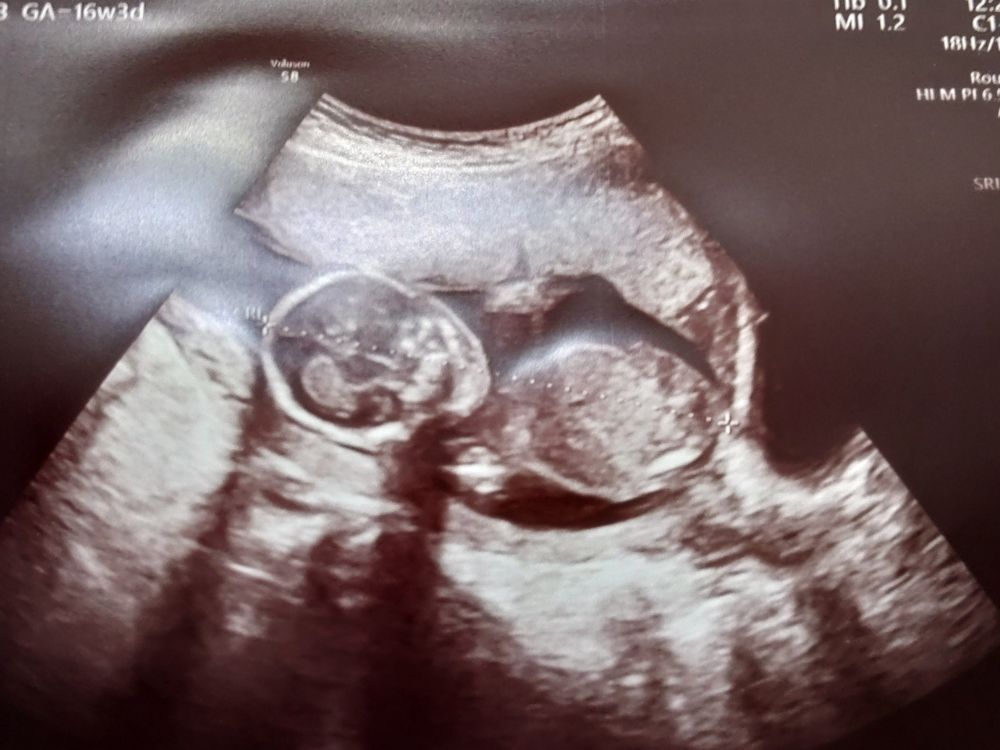

胎動を感じたのは離島に戻ってからの16〜17週ごろ。最初は「これかな?」というモニョモニョとした動きで、半信半疑でした。

でも、はっきりとポコポコ動くようになってからは、「生きているんだ」と強く実感できて、安心できるようになってきました。

不安は完全になくなるわけではないけれど、動きを感じるたびに「大丈夫だよ」と赤ちゃんに励まされているようで、本当に心強いです。